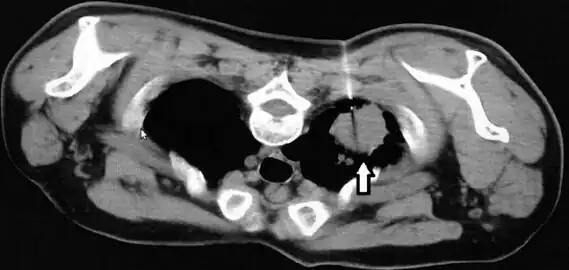

X-rays or CT scans can be used to examine the lung tissue, however it can not be used to positively diagnose geotrichosis. X-rays or CT scans may show cavitation that is located the walls of the lungs tissues. The results of imaging of pulmonary geotrichosis presents smooth, dense patchy infiltrations and some cavities.[3][12][3]

CT scan thorax revealed a soft-tissue mass with cavitation and surrounding consolidation at the right upper lobe